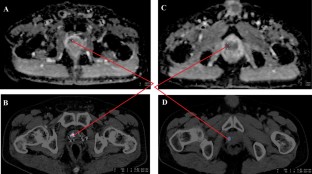

Fig. 1

Fig. 2

Fig. 3